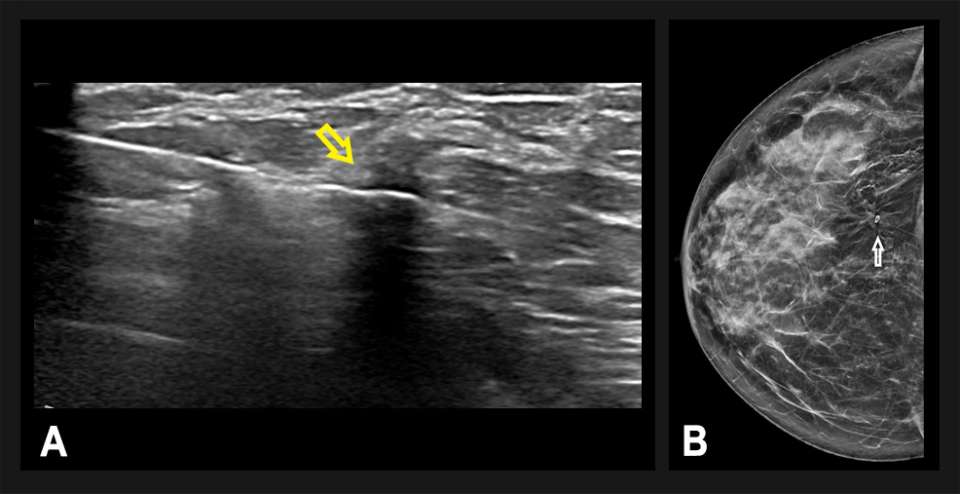

A technically-successful ultrasound-guided biopsy was performed, with 6 core samples obtained (Figure 3). A post-biopsy mammogram confirmed accurate positioning of the biopsy microclip at the site of architectural distortion. Pathology revealed invasive ductal carcinoma, grade 1 estrogen receptor negative, progesterone receptor negative, and HER2 positive. The patient underwent a right breast lumpectomy and sentinel lymph node biopsy, followed by adjuvant radiation.

Figure 3: Ultrasound-guided percutaneous biopsy was performed on the same patient, targeting the vague hypoechoic vague hypoechoic area seen on diagnostic breast ultrasound. (A) Using a coaxial percutaneous needle biopsy system, the abnormality was biopsied (yellow arrow) without complication. (B) Post-biopsy mammography demonstrated accurate placement of the biopsy microclip (white arrow). Pathology revealed invasive ductal carcinoma.